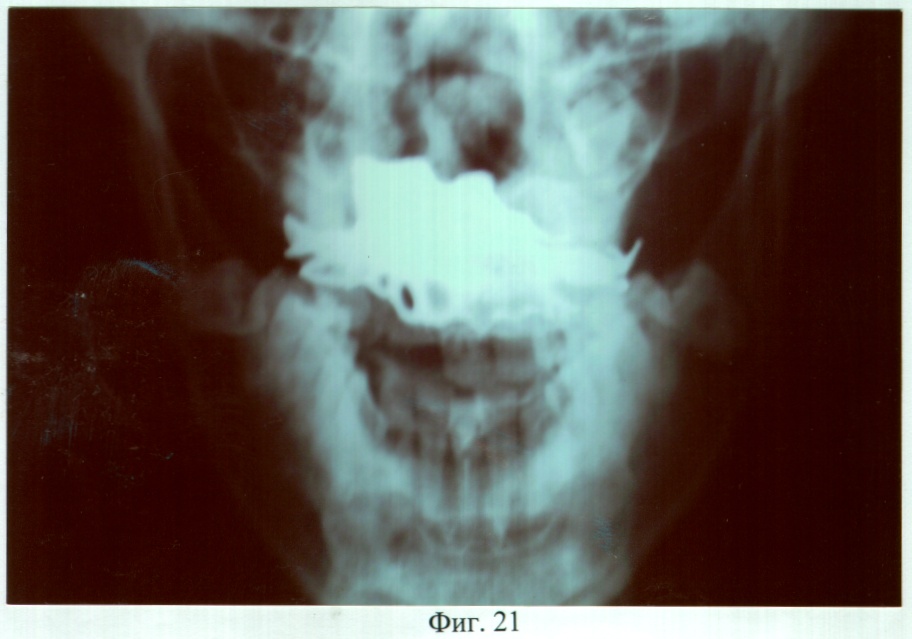

На фиг.21 – рентгенограмма больной С. через 3 года после ортопедического лечения (прямая проекция).

Адаптация к протезу наступила в течение семи дней, после чего больная отмечала удовлетворительное функциональное состояние зубочелюстного аппарата. Фонетическое обследование показало, что до ортопедического лечения нарушено произношение звуков – г, ж, к, п, р, т, ц, ч; k=5; U=21,3%. После протезирования нарушено произношение звуков – г, ж, к, р, ц; k=3; U=6,6%. При осмотре через 3 года больная жалоб не предъявляла, состояние протеза удовлетворительное. Морфологические исследования слизистой оболочки протезного ложа и рентгенография костей лицевого скелета, проведенные до и через 6, 12, 24 и 36 месяцев после протезирования, показали отсутствие признаков воспаления и прогрессирования атрофии.

С использованием данной технологии проведено ортопедическое лечение 5 больных, в возрасте от 26 до 63 лет. Адаптация к ортопедическим конструкциям протекала в сроки от 7 до 14 дней, после чего больные отмечали удовлетворительное функциональное состояние зубочелюстного аппарата. Во всех случаях получен удовлетворительный эстетический результат. Последующие клинические наблюдения в сроки 6, 12, 18, 24, 36 месяцев после протезирования не выявили функциональных нарушений, отзывы о протезах удовлетворительные. Анализ морфологических исследований слизистой оболочки протезного ложа до и в отдаленные сроки после ортопедического лечения позволил сделать вывод об отсутствии воспалительных явлений и признаков прогрессирования атрофии. Рентгенологических признаков дальнейшей атрофии костной ткани протезного ложа, связанной с протезированием, не выявлялось ни в одном случае. Сравнительные результаты фонетической диагностики и исследований жевательной эффективности по С.Е.Гельману между больными, протезирование которым выполнено конструкциями, изготовленными предложенным способом и традиционными, представлены соответственно в таблицах 1 и 2.